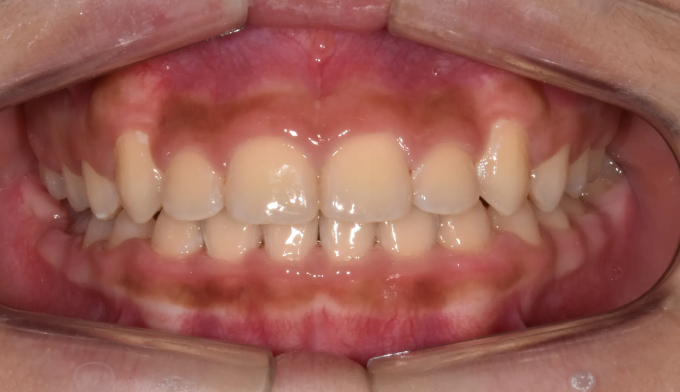

초등학교 4학년 남학생이 이가 고르지 못하고 송곳니가 나지 않는다고 합니다.

엑스레이를 찍어보니 치아가 나올 공간이 많이 부족하여 이가 고르지 못하고 송곳니가 나올 공간도 부족해 보였습니다. 정상적인 맹출 순서가 어긋나다보니 치열의 비대칭도 관찰됩니다.

약 8개월간의 공간확장치료를 통하여 이가 배열되고 송곳니가 나올 공간을 만들어주었습니다.

공간 확보 후 치아를 배열하여 교정 마무리 하였습니다.

총 교정기간은 22개월 소요되었습니다.